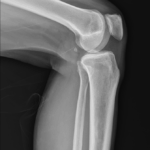

01 무릎 질환의 접근

1 무릎4하지Lower Extremities